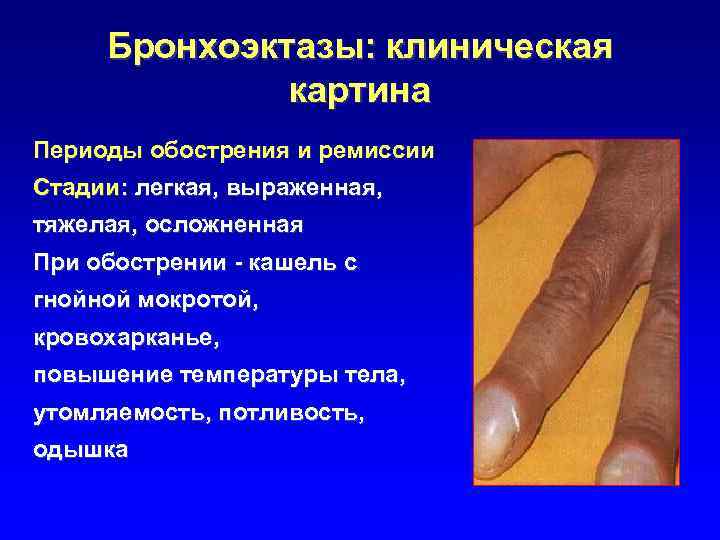

Бронхоэктазы: клиническая картина Периоды обострения и ремиссии Стадии: легкая, выраженная, тяжелая, осложненная При обострении - кашель с гнойной мокротой, кровохарканье, повышение температуры тела, утомляемость, потливость, одышка

Симптом «барабанных палочек» и «часовых стекол» при нагноительных заболеваниях легких